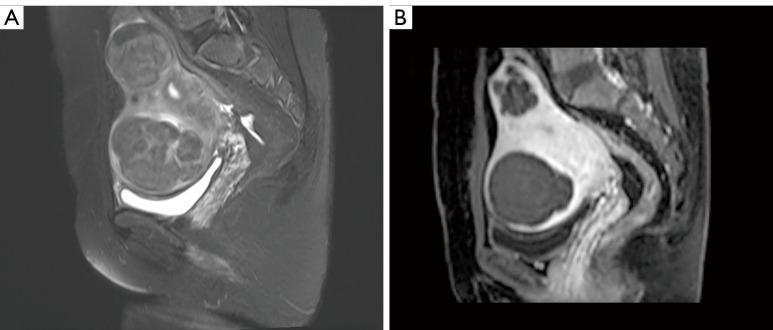

A retrospective cross-sectional study was conducted, involving imaging data from 194 patients diagnosed and treated with HIFU ablation for uterine fibroids at our institution. Patients were divided into the seromuscular-layer injury group and the intact group based on the presence or absence of perfusion defects on postoperative sagittal or axial enhanced T1-weighted imaging (T1WI) magnetic resonance images. Clinical and imaging traits potentially linked to seromuscular-layer injury were gathered and evaluated across the two groups.

The intact group comprised 139 cases, whereas the injury group comprised 55 cases. Logistic regression analysis revealed that subserous myoma (P=0.008), age ≤43.5 years (P=0.008), the thickness of the rectus abdominis muscle ≤8.06 mm (P=0.001), the energy efficiency factor ≤3.6 J/mm (P=0.002), the non-perfused volume ratio ≥67% (P=0.032), and the number of quadrants of peripheral muscle layer ≤1 (P=0.015) were the most significant influencing factors for seromuscular-layer injury in patients with uterine fibroids after HIFU treatment.